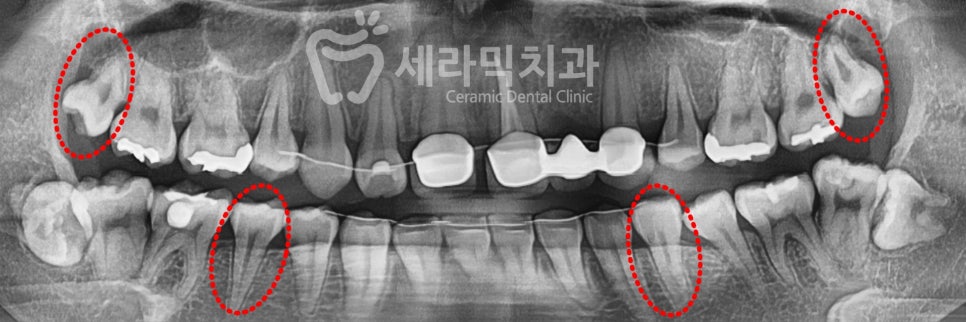

10대에 타 치과에서 치아교정을 하셨던 분으로,

치아교정 후 앞니(#22)를 상실하고 브릿지 치료를 하신 후

시간이 지나면서 치아가 돌출되고 앞니가 벌어졌습니다.

예전의 치아교정에서 위의 앞니 2개를 이미 발치하였기에,

돌출 개선을 위해 위쪽 사랑니 2개(#18, #28)와

아래쪽 작은 어금니(#35, #45)를 발치합니다.

미니스크류를 이용하여 위쪽의 심한 돌출을 개선합니다.

아래쪽의 사랑니는 크게 불편함이 없을 경우 발치하지 않고 진행합니다.